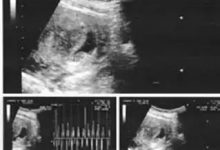

佛山*师兄夫妻俩都是原始点的高级粉丝。家里人日常不舒适都用原始点来解决,而且能做到手到病除,所以对原始点信心非常足。他们俩非常有爱心,也经常用原始点给亲戚朋友处理一些日常小毛病,以些来推广原始点。平时在用原始点遇到什么问题时会经常联系我来探讨原始点运用方面的细节。 2013年8月上旬,*师兄给我来电话说他夫人怀孕8周了,出现流血现象,经医院超声检查胎儿是终止妊娠了。以下是医院终止妊娠检查报告: *师兄给我来电话说:这种情况能不能用原始点来排出。我的回答是肯定的,并要求她夫人加强内外热源。抽时间过来,我来帮做原始点。 8月9日,他们夫妻俩就来到了我们服务中心,我更详细地了解了相关情况得知就是小腹坠胀痛外,...

原始点调理胎死腹中案例-唐小春  www.cch-foundation.com/html/custom/2020-11-10/1448.html 日期:2020/11/10  2020年4月16日孕检时,发现胎儿已无心跳,当时已怀孕12周,必须手术下胎。先生说原始点可以自然引产,我虽然质疑,但商量后,还是决定到原始点中心试试。  【 4月16日胎死腹中检查报告    中、晚期妊娠一般产前超声检查(I级)报告单难名:唐小春性别:年龄:38检查号:201621后来源:门诊临床科室;     仪器类型:GEE6201404A检查部位:产科1级彩超:13-15周(不含1的周)临床诊断;*******     检查所见:   ...